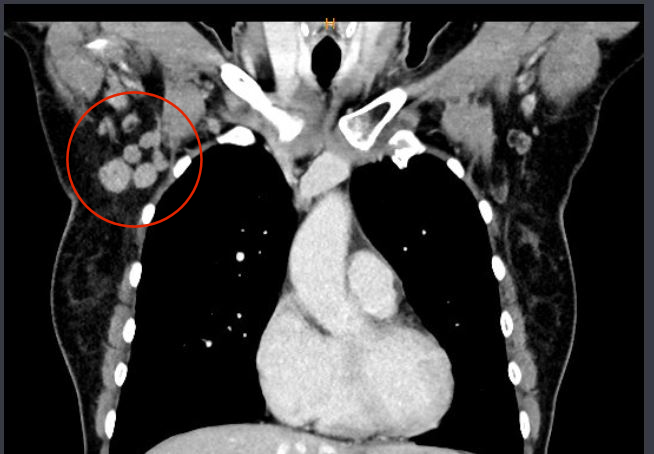

Er hätte vergessen: In der rechten Achsel zeigten sich mehrere bis zu 20 mm im Durchmesser

messende Lymphknoten, hier muss sicher primär von einer Metastasierung ausgegangen werden.

Er zeigt auf den Bildschirm. Ja, das hatte ich ja bereits befürchtet. Auf den Aufnahmen des CTs kann man ziemlich deutlich Brustkrebs und die betreffenden Lymphknoten erkennen, die dagegen auf der linken Seite unsichtbar sind.